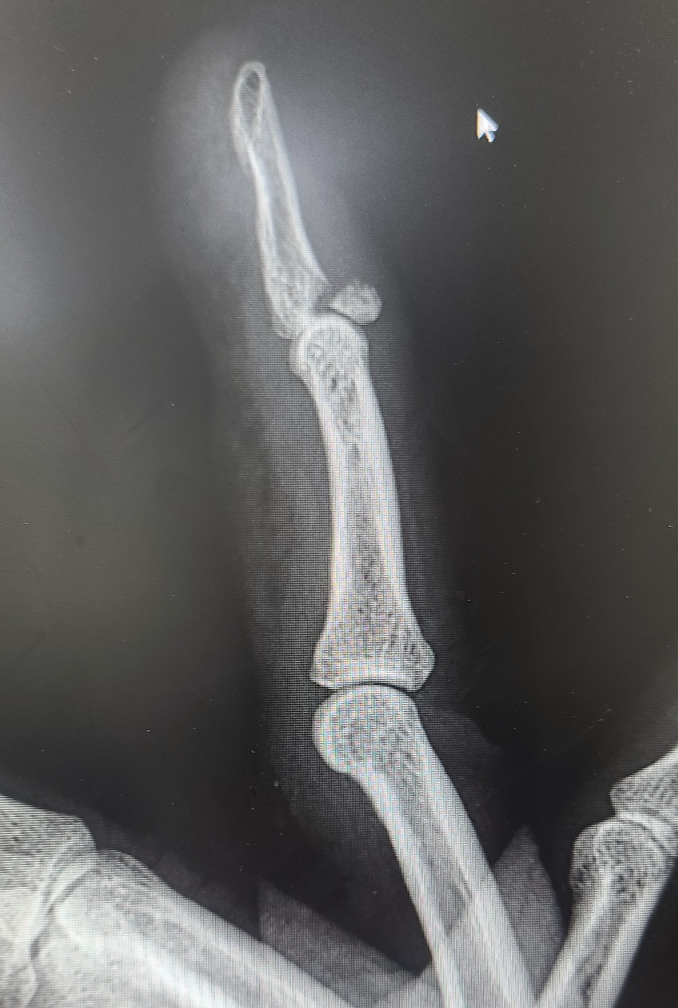

<손가락 골절>

<손가락 탈골>